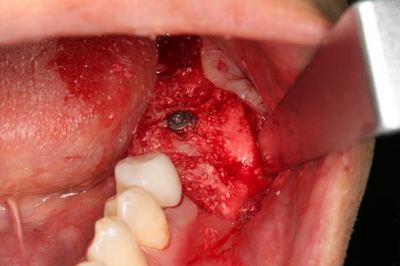

この段階で粘膜剥離して実際の骨の状態を確認します。

この部分は歯根破折と炎症のある歯を抜歯していますので

軟組織が存在し完全な骨性の治癒ではありません。

![]()

ドリリングを進め、軟組織を除去しました。

骨欠損部分には骨補填材を填入しますが、まずは埋入を行います。